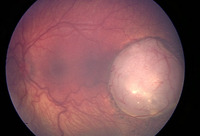

Macular retinoblastoma in the right eye

Personal collection of Dr Timothy Murray